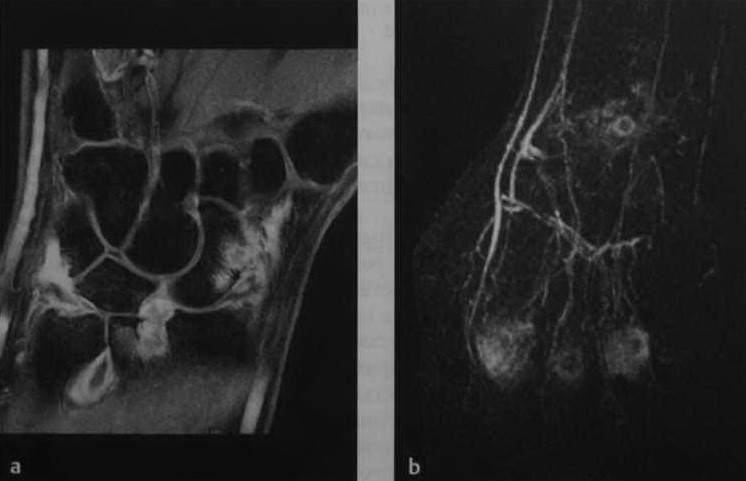

а, b Ревматоидный артрит . МРТ: A) Т1 - взвешенная SЕ-последовательность с подавлением МР-сигнала от жировой ткани после введения контрастного вещества. Накопле

Накопление контрастного вещества синовиальной оболочкой области запястья, так же как лучезапястного и дистального локтезапястного сустава. Поражение ладьевидно-полулунной связки и эрозирование ладьевидной кости; b) Динамическая контрастно-усиленная МРТ у другого пациента. Раннее артериальное контрастное усиление вокруг II—V пястно-фаланговых суставов и суставов запястья, являющееся признаком выраженного воспалительного процесса.